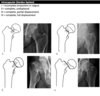

A

Pneumothorax

How well did you know this?

1

Not at all

2

Intracapsular (Garden classification)

Extracapsular (intertrochanteric) fracture

135

Extracapsular (subtrochanteric) fracture

Dynamic hip screw (DHS)

Hip replacement

Extracapsular NOF